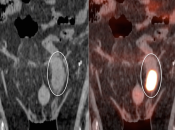

Bladder Hernia

While the CT appearance of this finding should never be missed, its striking PET appearance has led more than one PET/CT reader astray.

Usually, the supero-lateral margin of the bladder will be seen partially entering the inguinal canal. Occasionally, a significant segment of the bladder may extend deep into the hernia defect.

Caveat: Never be duped by an unusual focus of intense metabolic activity anywhere in the body. Always rule out every possible non-neoplastic explanation before raising the specter of cancer.